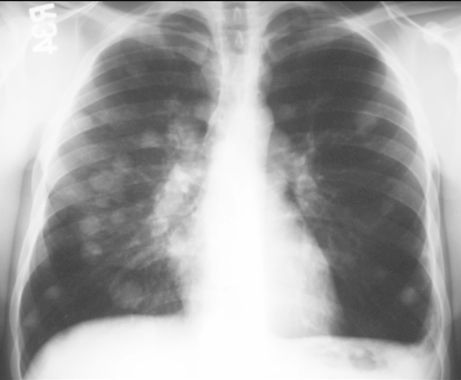

PRZERZUTY DO PŁUC

RTG